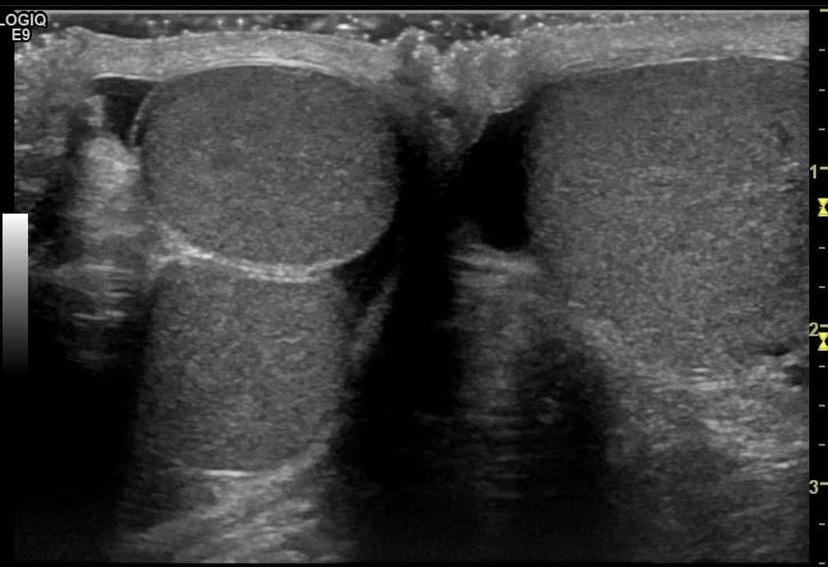

Polyorchidism or supernumerary testicles is a rare condition with the presence of an accessory testis, can be unilateral or bilateral. It is believed to occur due to abnormal development of the genital ridge in the 8th week of fetal development.

75% of cases represent as a painless palpable mass in the scrotum. [1]

Thereis usually 3 testes with the extra testicle usually located in the LT in 64.5 % of cases. [2]

There can also be 4 testicles (4.3% of cases)